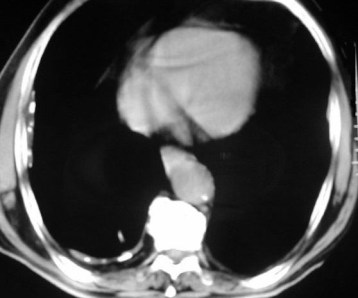

SIGNO DE LA S DE GOLDEN

Imagen en forma de «S» itálica que forma el margen cóncavo del lóbulo superior derecho colapsado (flecha roja) y el margen convexo de una masa hiliar derecha (flecha blanca) causante del colapso. En el colapso de otros lóbulos hay imágenes equivalentes a la «S» de Golden, pero no tan gráficas.

En la fotografía, tumor epidermoide hiliar derecho.